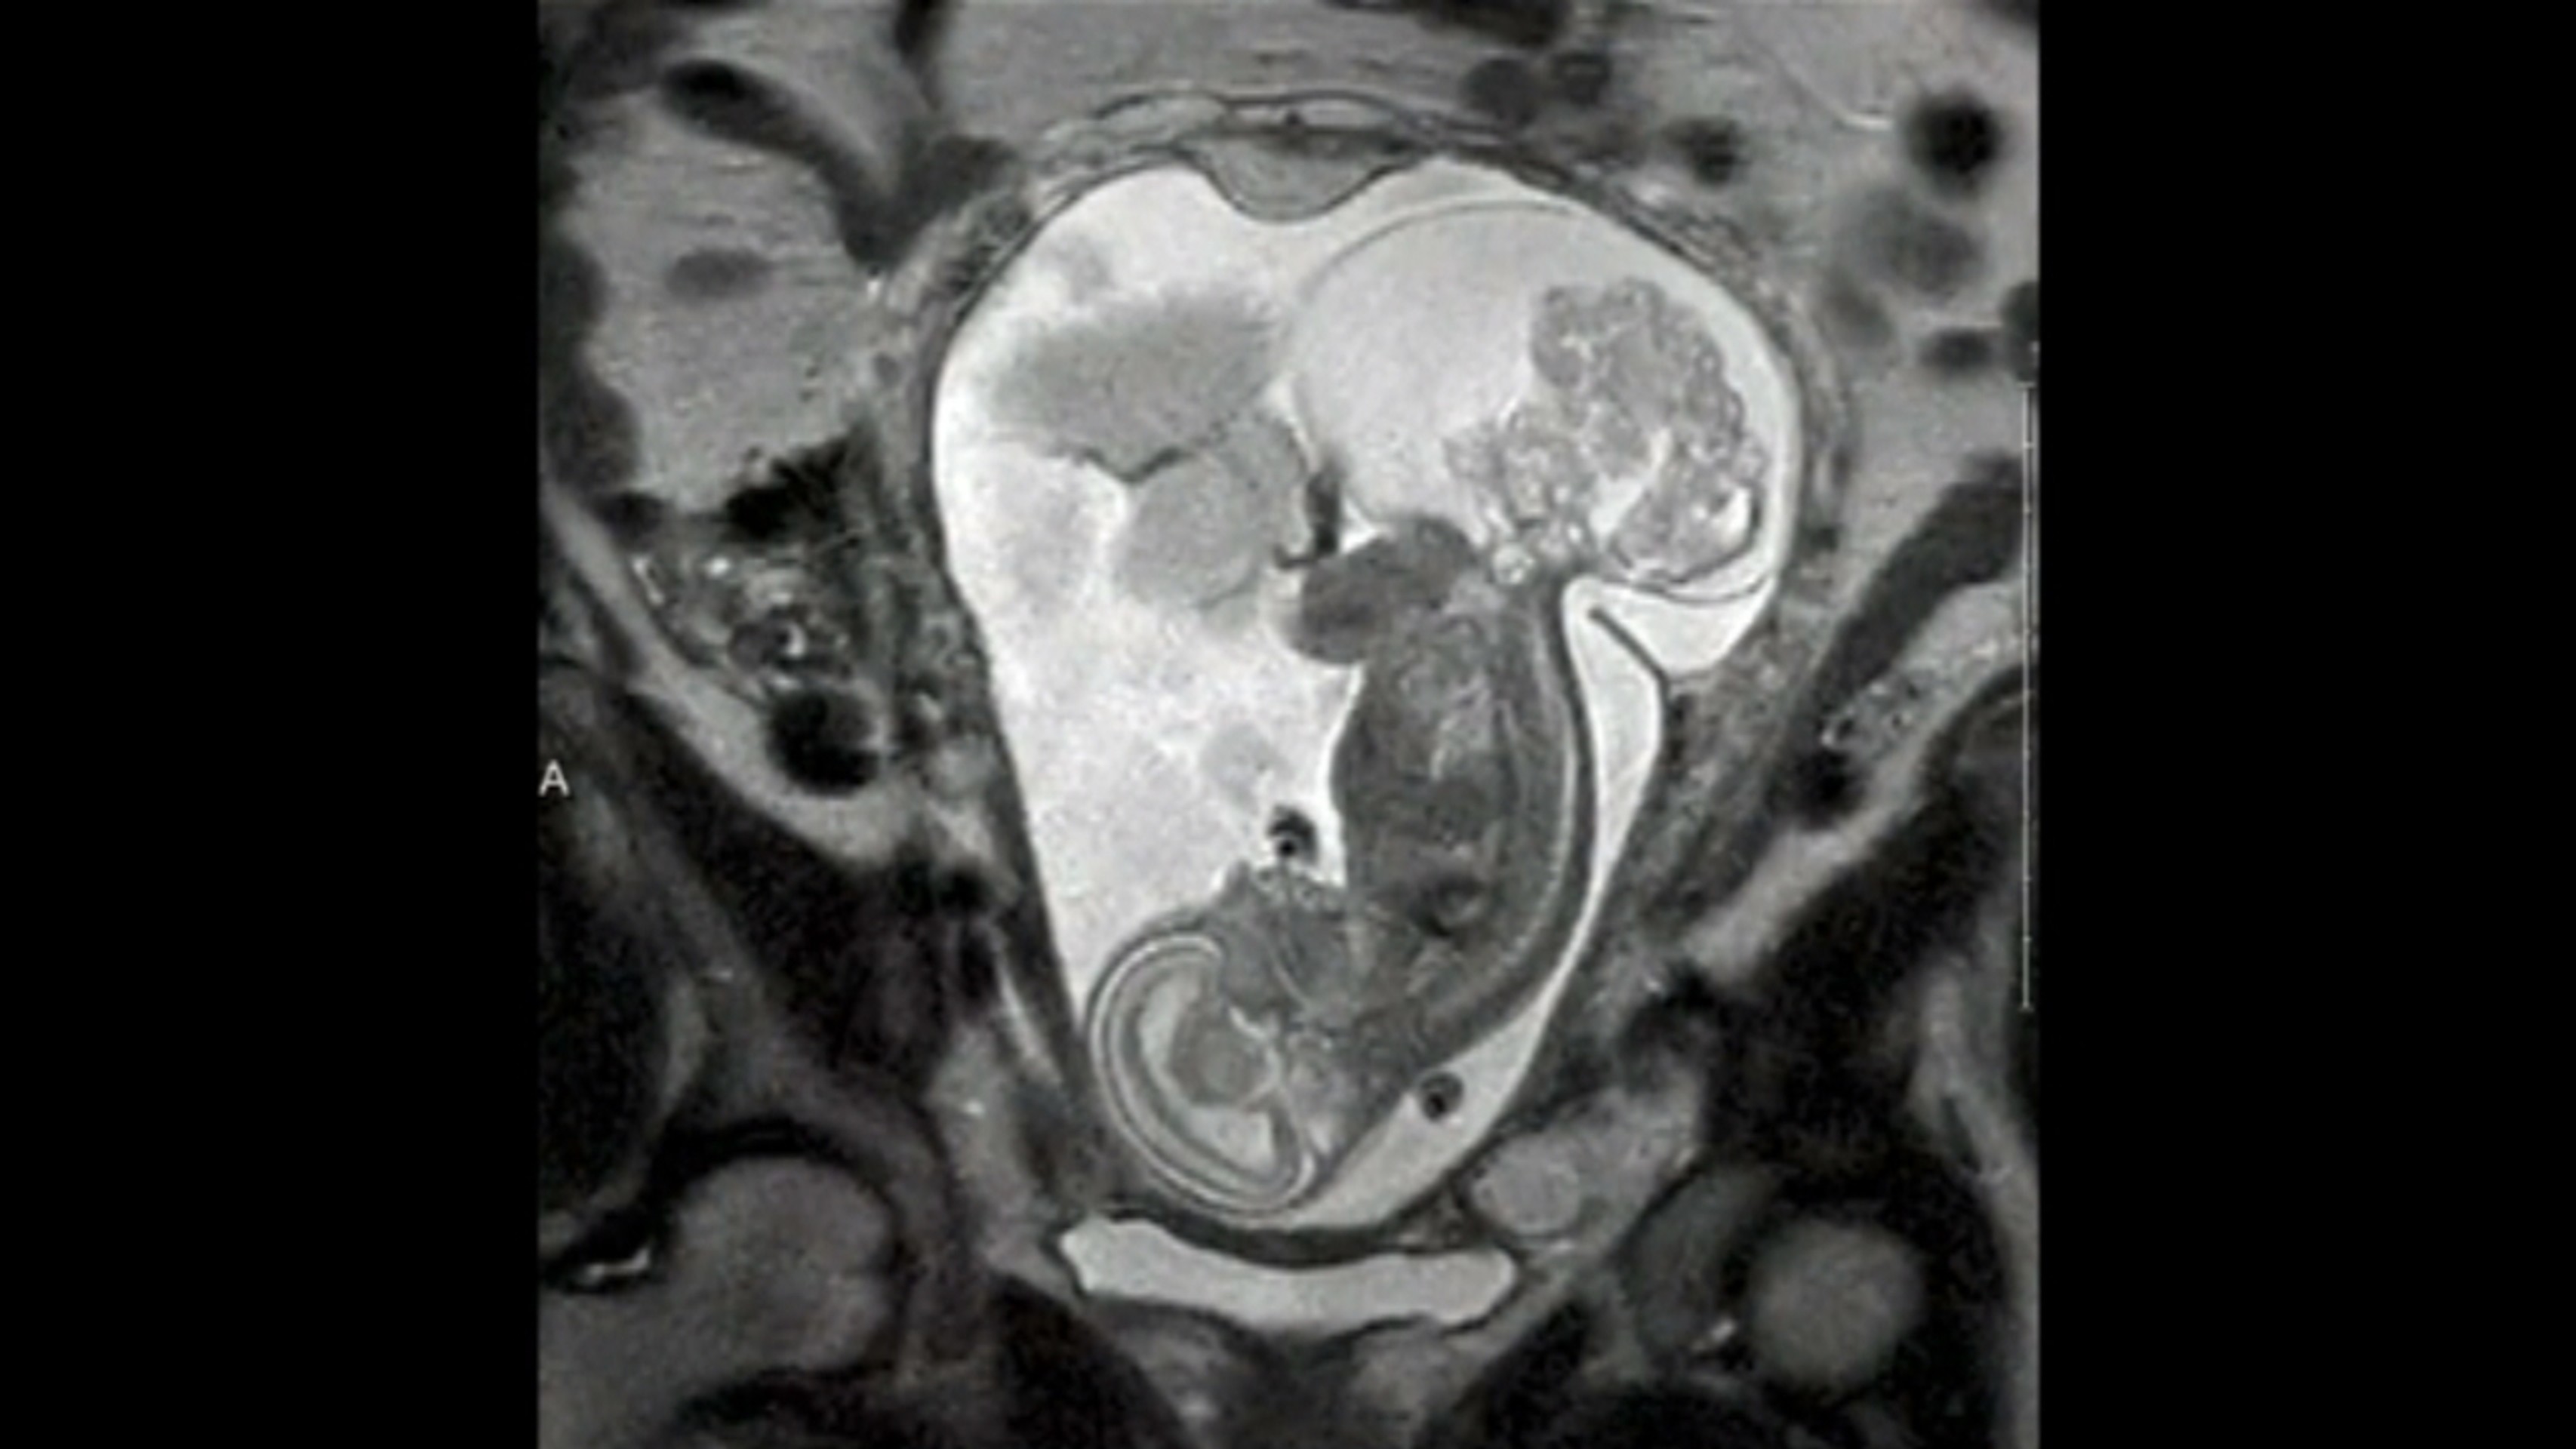

Dieťa a tumor

Zdroj: Reuters